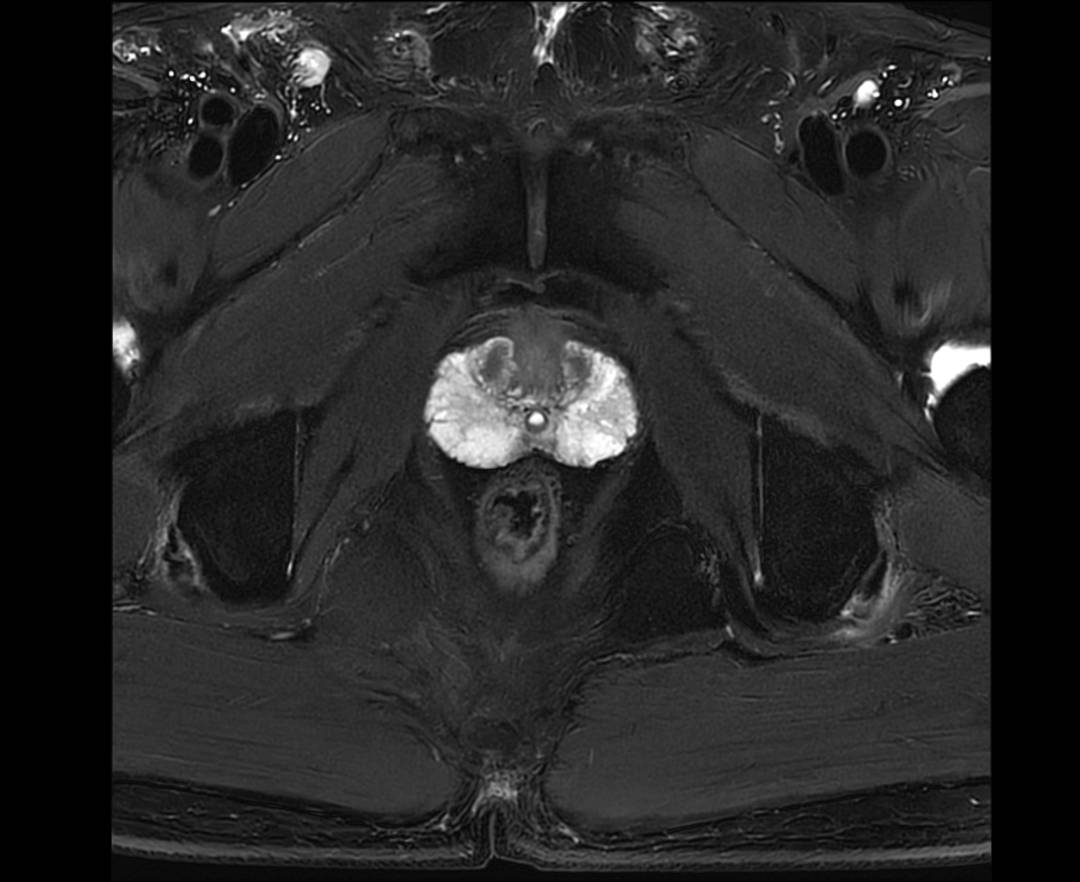

PROSTATE T2 FS TRA

PROSTATE T2 TRA